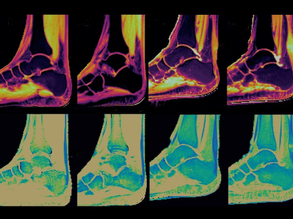

Feet First